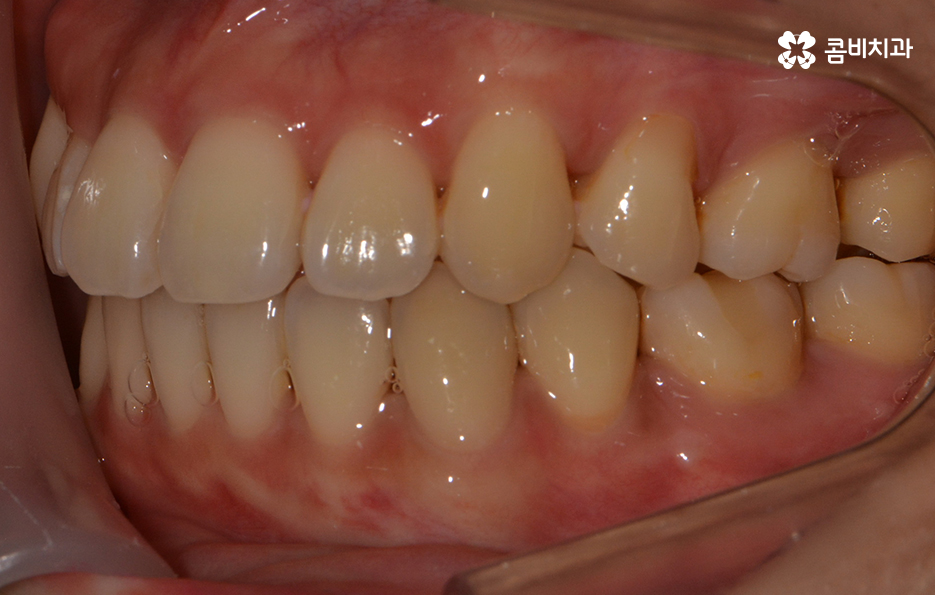

콤비교정이 마무리된 후 장치를 풀어낸 모습

처음부터 교정치료를 알아보실 때 얼굴 변화를 생각하여

알아보시는 분들도 많이 계시지만

불규칙한 치열로 인해서 치열의 개선만을 먼저

생각해고 교정을 알아보시는 분들도 계실 텐데요.

누구라도 교정치료를 받을 때 얼굴과 골격을 함께

생각한 치료 계획을 세우는 것이

보다 건강하고 얼굴과의 조화를 위해서도 중요합니다.

교정 장치를 풀어낸 후 유지 장치를 부착한 상태